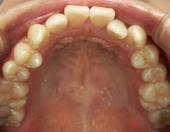

主訴:奥歯で噛んだときに前歯が噛み合わない

━━ 当院で働いている池谷彩乃さんが、前突および開咬を舌側ワイヤー矯正で治療しました。

中学生になり第二大臼歯が生えてから、真ん中の前歯2本が出てきて、八重歯も目立つようになりました。はじめは八重歯がチャームポイントだと捉えて気にしていませんでしたが、年々歯並びが悪化している気がしました。そのうち前突が原因で口が閉じづらく、寝ている時は口呼吸になってしまいました。

高校時代には、歯並びを改善しようと様々な矯正サイトを閲覧し、自分自身が開咬であることを知りました。開咬とは、上下の歯を噛み合わせた時に前歯に隙間ができることを言います。そういえば、麺を前歯で噛みきること、ハンバーガーにガブッと噛みつくことができませんでした。